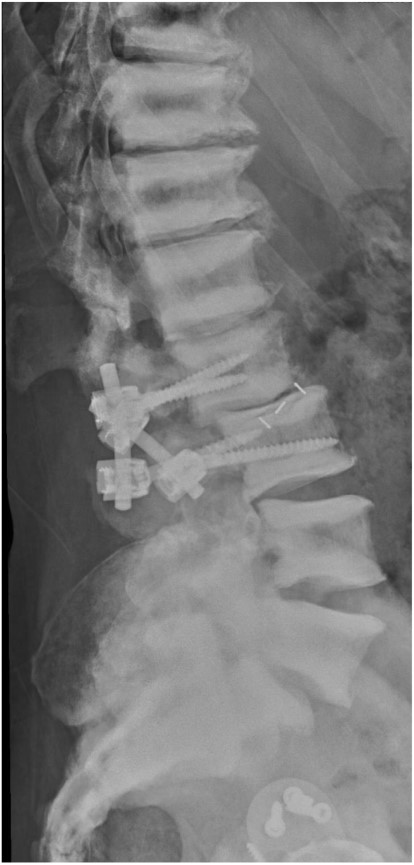

Six months later, he complained about lumbar pain which irradiated into the right thigh and knee. A CT scan of the lumbar spine showed multiple lumbar spine stress fractures, and CT myelography showed complete obstruction at L2–3 level (Figs 4 and 5). Conservative therapy was ineffective. Therefore, the patient was transferred to a spinal center. There he underwent L2–L3 decompression with short-term effect because decompression resulted in instability. 360° spondylodesis was done; however, it resulted in non-union, and the material was removed (Fig. 6).

Lateral radiograph of the lumbar spine after failed 360° spondylodesis.